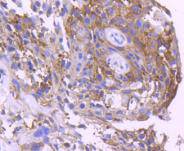

14-3-3 sigma Rabbit mAb

WB, IHC

WB: 1:1,000

IHC: 1:50-1:200